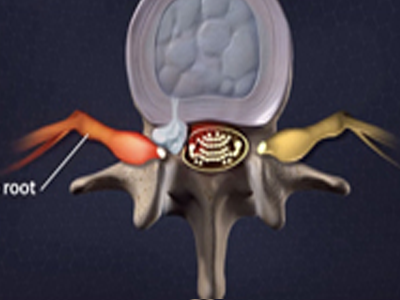

脊柱脊髓神經(jīng)微創(chuàng)中心以微創(chuàng)技術(shù)為引領(lǐng),以功能恢復(fù)為目標(biāo),主要治療脊柱外傷、腫瘤、退行性病變、脊柱畸形等疾病。團(tuán)隊(duì)利用神經(jīng)外科顯微技術(shù),結(jié)合神經(jīng)內(nèi)鏡微創(chuàng)技術(shù),對(duì)脊柱間盤變性疾病、頸腰椎管狹窄、頸腰椎間孔狹窄、頸腰椎間盤突出、頸腰椎體不穩(wěn)、脊柱骨折、寰樞椎脫位、脊柱腫瘤、椎管內(nèi)腫瘤、脊髓損傷、脊髓空洞、脊髓栓系等疾病進(jìn)行高效、特色手術(shù)治療,如顱頸交界區(qū)畸形寰枕減壓內(nèi)固定術(shù)、脊柱腫瘤全脊椎切除內(nèi)固定術(shù)、微創(chuàng)椎管內(nèi)腫瘤切除術(shù)、微創(chuàng)脊柱旁腫瘤切除術(shù)、寰樞椎脫位椎間融合內(nèi)固定術(shù)、脊柱骨折微創(chuàng)經(jīng)皮椎弓根釘內(nèi)固定術(shù)、經(jīng)椎間孔椎間融合內(nèi)固定術(shù)(MIS—TLIF)等,最大程度降低脊柱脊髓手術(shù)創(chuàng)傷,具有創(chuàng)傷小、輸血少、恢復(fù)快、口碑好,出院早等優(yōu)勢(shì)。